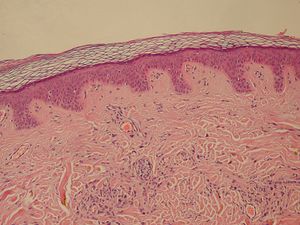

Normal Epidermis and Dermis with Intradermal Nevus 10x-cropped | |

خلايا ميلانينية | وحمة | |